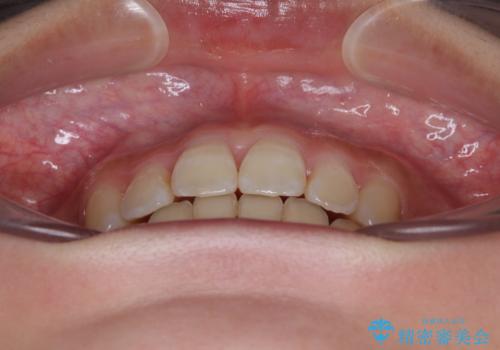

- 前歯のデコボコと唇の閉じにくさを気にして来院された患者様です。

単純に上下左右の第一小臼歯4本を抜歯して口元の突出感を改善することも考えられましたが、上顎骨よりも下顎骨の幅が広いため、より良い咬み合わせを達成することを目的として、急速拡大装置を用いて上顎骨を拡大することとしました。

歯列矯正では基本的に骨格を改善することはできませんが、急速拡大装置(MARPE)を使用することで上顎骨を側方に拡大させることができ、咬合状態を大きく改善することができます。